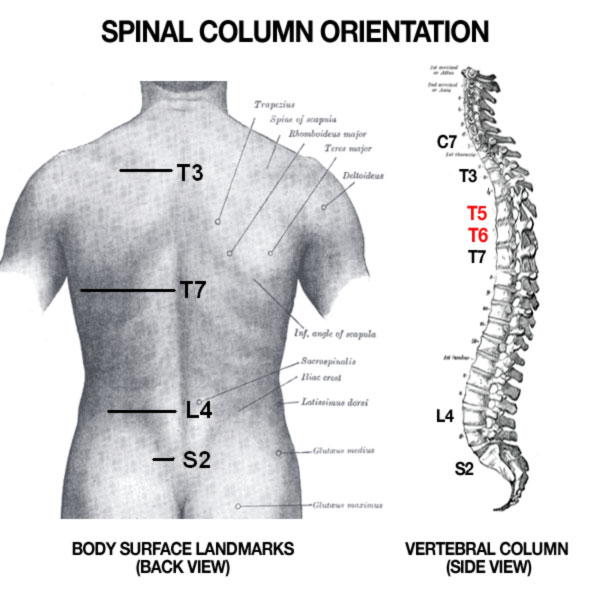

diagram of cervical and thoracic spine – Google Search | Spinal cord …

Pin by G Wilk on Anatomy and Physiology | Medical anatomy, Human …

Diagram showing the relationship between spinal nerve roots and …